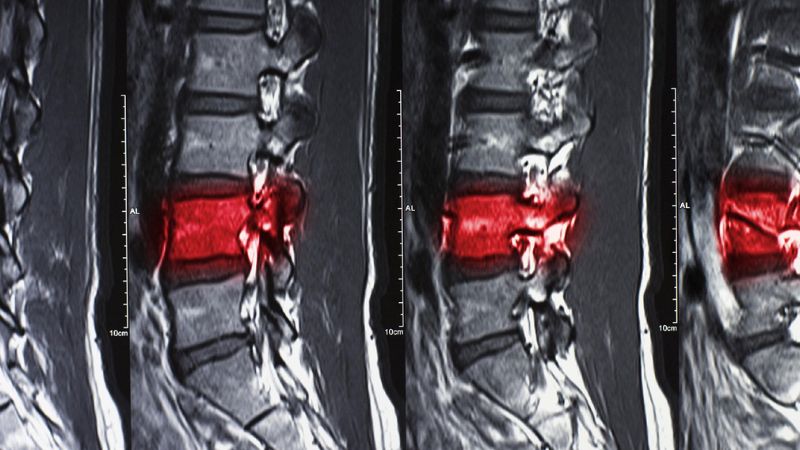

- Liệt tuỷ, gãy cột sống

Người bệnh có thể gặp các biến chứng như gãy cột sống